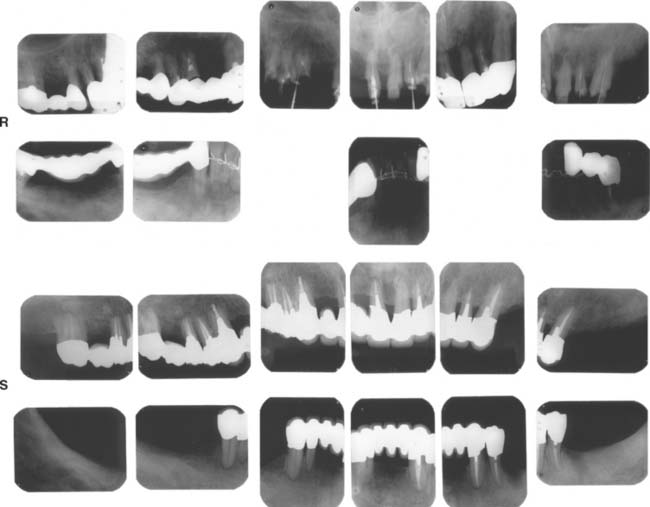

Fig. 32-42 This patient presented with multiple failing restorations and severely compromised function (Treatment X). A to E, Preoperative photographs. F to J, Posttreatment photographs. Where possible, I-bars were used to minimize clasp visibility. Also note the extensive use of metal occlusal surfaces. When prostheses are designed for dentitions with compromised crown/root ratios, precise adjustment of the occlusion and anterior guidance components is critical. K to Q, Seventeen-year follow-up photographs. Note that the maxillary canine was lost and the existing retainer was modified into a pontic through the addition of composite resin. Additional endodontic treatment was needed as time passed. R, Preoperative radiographs. S, Postoperative radiographs. T, Eight-year postoperative radiographs. U, Seventeen-year postoperative radiographs. A fixed dental prosthesis (FDP) was fabricated, replacing the missing tooth #3 with teeth #5, #4, and #2 as abutments. The teeth were prepared with minimal taper, and the castings exhibited good retention. After 10 years, the FDP failed when tooth #2 became dislodged, possibly as a result of the additional loading by the removable dental prosthesis (RDP). Tooth #2 and the pontic were removed, endodontic treatment was performed, a new crown was fabricated, and the #3 pontic was incorporated in a new RDP. Tooth #6 was lost as a result of internal resorption and caries. Initially, the tooth was discolored, but the lesion was inactive, and the attempt to save it failed after 8 years. Its guarded prognosis was discussed as a significant risk factor before treatment initiation. This suggests that teeth with a guarded prognosis can be maintained if attention is paid to the principles of casting adaptation and occlusion.